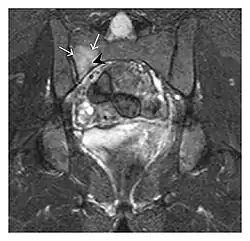

The sacrum is usually masked by overlapping bowel gas in conventional radiographs, and the subtle radiographic findings are usually nondiagnostic and even misleading. The characteristic "H" pattern has been correlated with biomechanical models of patient activities. The vertical parasagittal planes correspond to the region of maximal stress during walking, while the horizontal fracture develops later, secondary to the loss of lateral support by parasagittal fractures. MRI is the primary imaging technique in this case, with the most common MRI pattern showing bone marrow edema and a fracture line (Figure 12). Coronal views are quite contributive in sacral fractures, allowing the detection of the horizontal component, especially with fluid-sensitive sequences. Although the sacrum is the most commonly involved, pelvic insufficiency fractures are often multiple, and other typical locations should be mentioned.[1]

Proximal femoral fractures usually occur in osteoporotic patients, and their signs include subtle neck angulation, trabecular angulation, and subcapital impaction line. A frog-leg lateral view may be helpful if the greater trochanter is short enough. However, positioning can be difficult because of hip pain. In patients with strong suspicion of proximal femoral fracture and negative radiographs, MRI limited to coronal T1 W images and scintigraphy can be highly valuable (Figures 13 and 14). Such an option, with limited examination time, is cost-effective and allows reliable exclusion or confirmation of the diagnosis, preventing an unnecessary stay at the hospital or delayed treatment. Moreover, MRI helps to detect soft tissue abnormalities which are more frequently seen in femoral, acetabular, and pubic injuries than sacral lesions. Concomitant fractures are also frequently seen in typical pelvic sites.[1]

Figure 13: Partial osseous avulsion of the gluteal muscles at the greater trochanter in a 59-year-old man who presented with the right hip pain without a history of trauma. Lauenstein view and anteroposterior and radiographs (not shown) did not show an obvious fracture line or disruption of bony contours in the acetabulum or the right femoral neck. (a) Coronal T1-weighted MRI displays an incomplete fracture line extending partially from the greater trochanter (arrow). (b) Coronal short tau inversion recovery MRI shows heterogeneous hyperintensity in the same region (arrow) as well as hyperintensity within the gluteus medius and minimus muscles (arrowheads) consistent with tissue edema and hematoma.[1]

Figure 14: Subcapital insufficiency fracture in a 55-year-old man with a left hip pain without a history of trauma. Anteroposterior and Lauenstein view radiographs centered on the left hip do not show an obvious fracture line, but mild acetabular osteophytosis was noted consistent with hip osteoarthritis (not shown). (a) Coronal T1-weighted MRI shows a linear low-signal band through the femoral neck corresponding to a fracture line (arrowheads). (b) Bone scintigraphy shows focal uptake (arrow) corresponding to the fracture.[1]